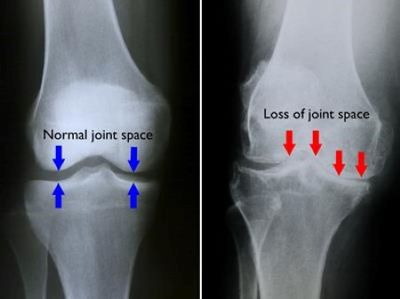

1.HYALURONIC ACID

Injections of Hyaluronic Acid have been found to be safe, effective, appropriate treatment for osteoarthritis. Patients typically experience at least 50 percent improvement in pain and function after 3-5 injections. Study: “US-Approved Intra-Articular Hyaluronic Acid Injections are Safe and Effective in Patients with Knee Osteoarthritis: Systematic Review and Meta-Analysis of Randomized, Saline-Controlled Trials (2013),"

2.PLATELET RICH PLASMA

Platelet Rich Plasma, or PRP, is a liquid made up of concentrated platelets from your own blood which are rich in healing and growth factors. Injections of PRP have been determined to be both safe and effective in treating osteoarthritis pain, and may slow or stop further degeneration of the joint. Study: “Effects of platelet rich plasma in combination with hyaluronic acid in the treatment of primary knee osteoarthritis”. Presented at: World Congress on Pain 2018; September 12-16, 2018; Boston, MA.

3.BRACING TO INCREASE JOINT SPACE

Arthritis “unloader” knee braces are ideal for relieving osteoarthritis knee pain and other knee symptoms that result from arthritis. They also help with knee stability during walking and help encourage mobility in patients. If worn as prescribed, these brace will “unload” the weight borne by the knee and help increase the space in the knee joint. Arthritis.org – “Living with Arthritis"